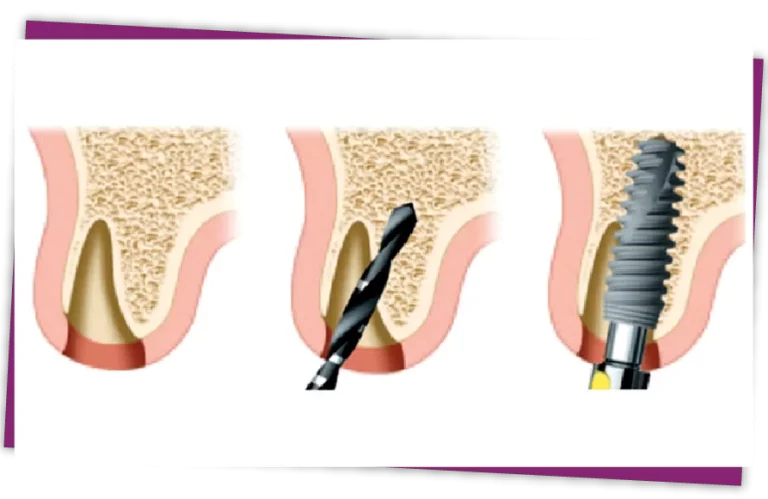

IMPLANT PLACEMENT PROCESS

The surgeon exposes the root, using a non-traumatic extraction technique to gently remove the root without damaging the alveolar bone and gum tissue.

After taking the teeth out, the surgon will place the Implant and add bone graft if necessary.

During the implant placement surgery, the alveolar bone is in an ideal state to place the Implant. If the extraction is done not in accordance with the technical expertise, it will be easy to break the alveolar bone, and it will take time to regenerate before implantation. Therefore, it is necessary to extract teeth using non-traumatic techniques, to ensure that the alveolar bone and gum tissue are not damaged.